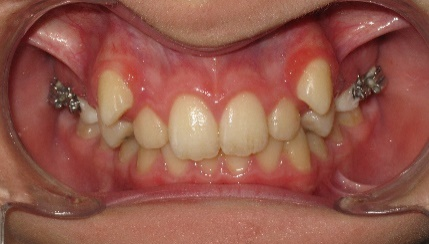

В последующем, после дистализации моляров на верхней челюсти, аппарат снят и на втором этапе ортодонтического лечения фиксирована брекет-система пассивного самолигирования NexStep Pro с пазом 0.22 (стандарт). Уникальная конструкция замка-слайда обеспечивает повышенный контроль торка и ротации, а прецизионность паза брекета дает полную реализацию программы, заложенную в брекетах данной системы SLS. (рис.6 )

На завершении проведения этапа нивелирования начинается активная дистализация первых и вторых премоляров на верхней челюсти с помощью открывающих пружин, выполненных из сплава NiTi c незначительной силовой нагрузкой. (рис.7.)

Рис.7. Этап нивелирования на аппарате NexStep Pro 0.22